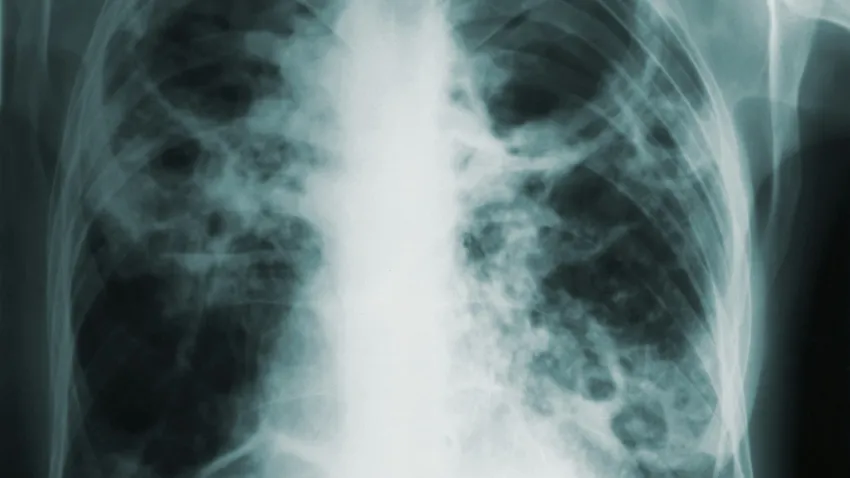

România se confruntă în continuare cu o rată ridicată a tuberculozei (TBC), situându-se printre țările din Regiunea Europeană a OMS cu cele mai multe cazuri. Pentru a atrage atenția asupra acestei probleme de sănătate publică, Arcul de Triumf din București va fi iluminat în roșu pe 24 martie, între orele 19:00 și 22:00. Evenimentul este organizat în parteneriat cu Primăria Municipiului București și Centrul de Cultură „Palatele Brâncovenești”.

Iluminarea Arcului de Triumf în roșu este o acțiune simbolică menită să arate solidaritatea cu persoanele afectate de TBC și să sublinieze importanța menținerii acestei probleme pe agenda publică. Ziua de Luptă Împotriva Tuberculozei este marcată anual pe 24 martie, fiind o prioritate de sănătate publică cu un impact major asupra societății. În 2021, OMS a estimat că aproximativ 4,1 milioane de persoane din întreaga lume sufereau de tuberculoză, dar nu fuseseră diagnosticate sau declarate oficial ca având această boală.

Tuberculoza este o boală infecțioasă care poate fi tratată dacă este depistată la timp. Cu toate acestea, vindecarea nu conferă imunitate, motiv pentru care prevenția rămâne esențială.